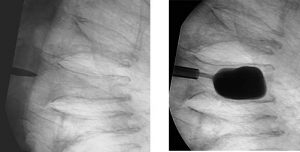

A new technique of percutaneous stabilization of vertebral fractures [Kyphoplasty], however, allows for restoration of the vertebral body height with injection of cement to stabilize VCFs. The patient is placed in a prone position. Using fluoroscopy, the surgeon introduces a cannula into the vertebral body through the pedicle posteriorly. A balloon is subsequently utilized to inflate and “jack up†the vertebrae to its normal, non compressed height. Subsequently, cement is injected into the void to prevent future collapse. [Figures 1 and 3].

Figure 2 and 3: With Kyphoplasty, a tube is introduced into the broken vertebrae which can be lifted back to its pre-fracture shape.